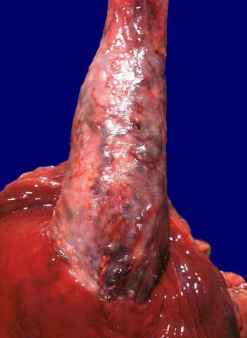

Diagnosi: Acalasia

Descrizione: Vista dal lato dorsale del pacchetto

polmonare con l’esofago massivamente dilatato.

Commento: Massiccia dilatazione della radura esofagea

a causa di danni acquisiti alle cellule gangliari nella

parete esofagea.